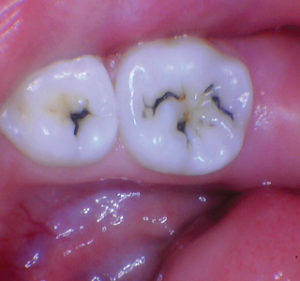

Caso 1

Un paciente de 8 años presentó descomposición de OD en un primer molar primario con síntomas de pulpitis reversible. El diente fue el tratamiento planificado para una restauración de OD con Activa Bioactive Restorative (Pulpdent). Tras la excavación por descomposición, se produjo una exposición pulpar que requirió una pulpotomía terapéutica. Debido a la edad del paciente, me sentí cómodo con una pulpotomía terapéutica con Biodentine (Septodont) seguida de una restauración estética. Si el paciente hubiera tenido entre cuatro y cinco años, me habría restaurado con una corona de acero inoxidable debido a su historial comprobado de longevidad.

Figura 1 Vista preoperatoria del primer molar primario superior. |